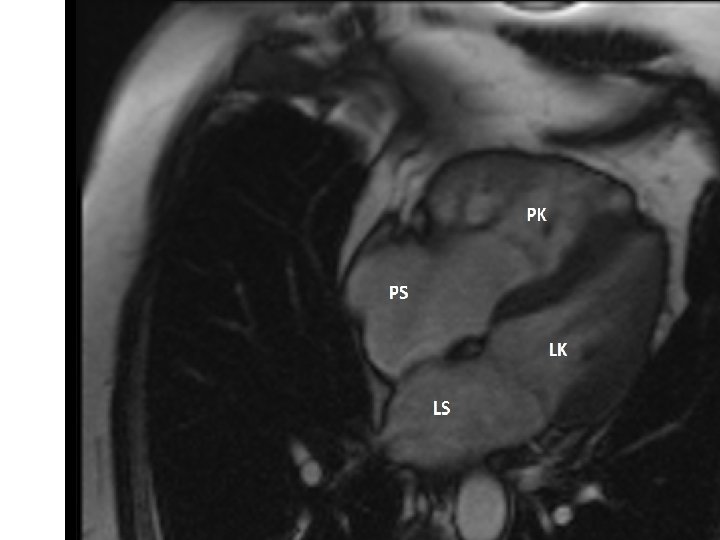

Transpozice velkých tepen s ASD, VSD